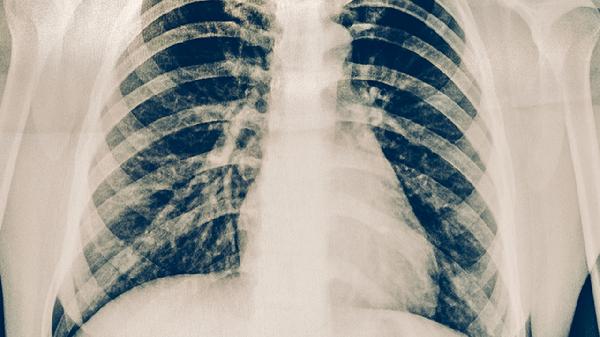

胸肋骨骨折吃什么能快速恢复